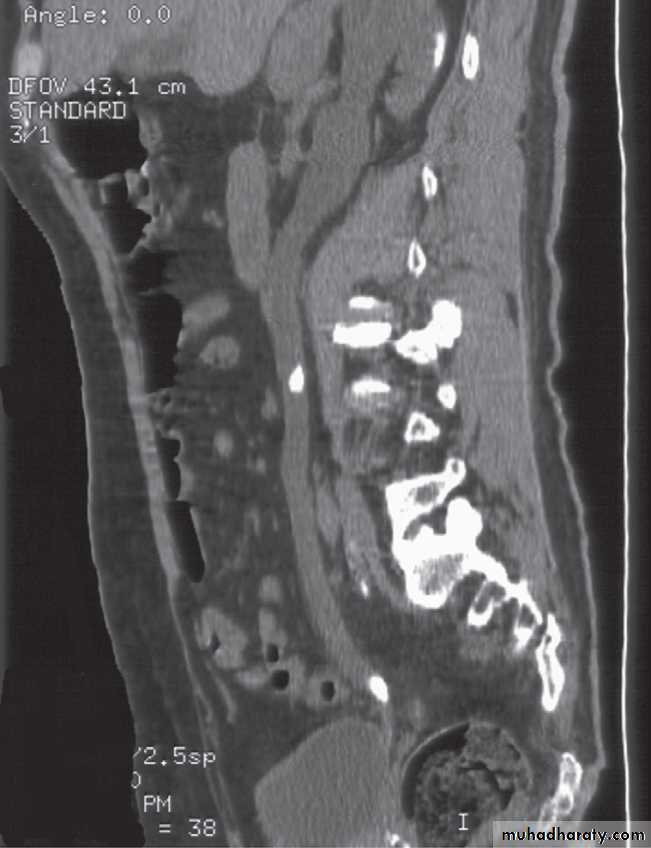

Computed tomography is now widely used to evaluate urinary tract obstruction .In acute obstruction, non-contrast enhanced CT sensitively demonstrates calculi and the unopacified, dilated collecting system can frequently be traced down to the point of obstruction .

Non-contrast CT is often used in acute ureteric colic, as an alternative to IVU, in patients with an allergy to intravenous contrast medium.

-Retroperitoneal fibrosis. In most cases, no cause can be found for this benign fibrotic condition, which encases the ureters and causes obstruction. When first seen, only one side may be obstructed but, eventually, the condition becomes bilateral.

The obstruction is usually at the L4/5 level. Fibrosis may extend superiorly to surround the kidneys and inferiorly to involve the pelvic side walls. CT has become the diagnostic method of choice.